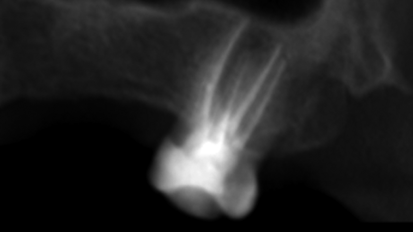

Historically, when a patient’s dental condition reached a state of total tooth loss, treatment was limited to a complete denture with no hope of ...